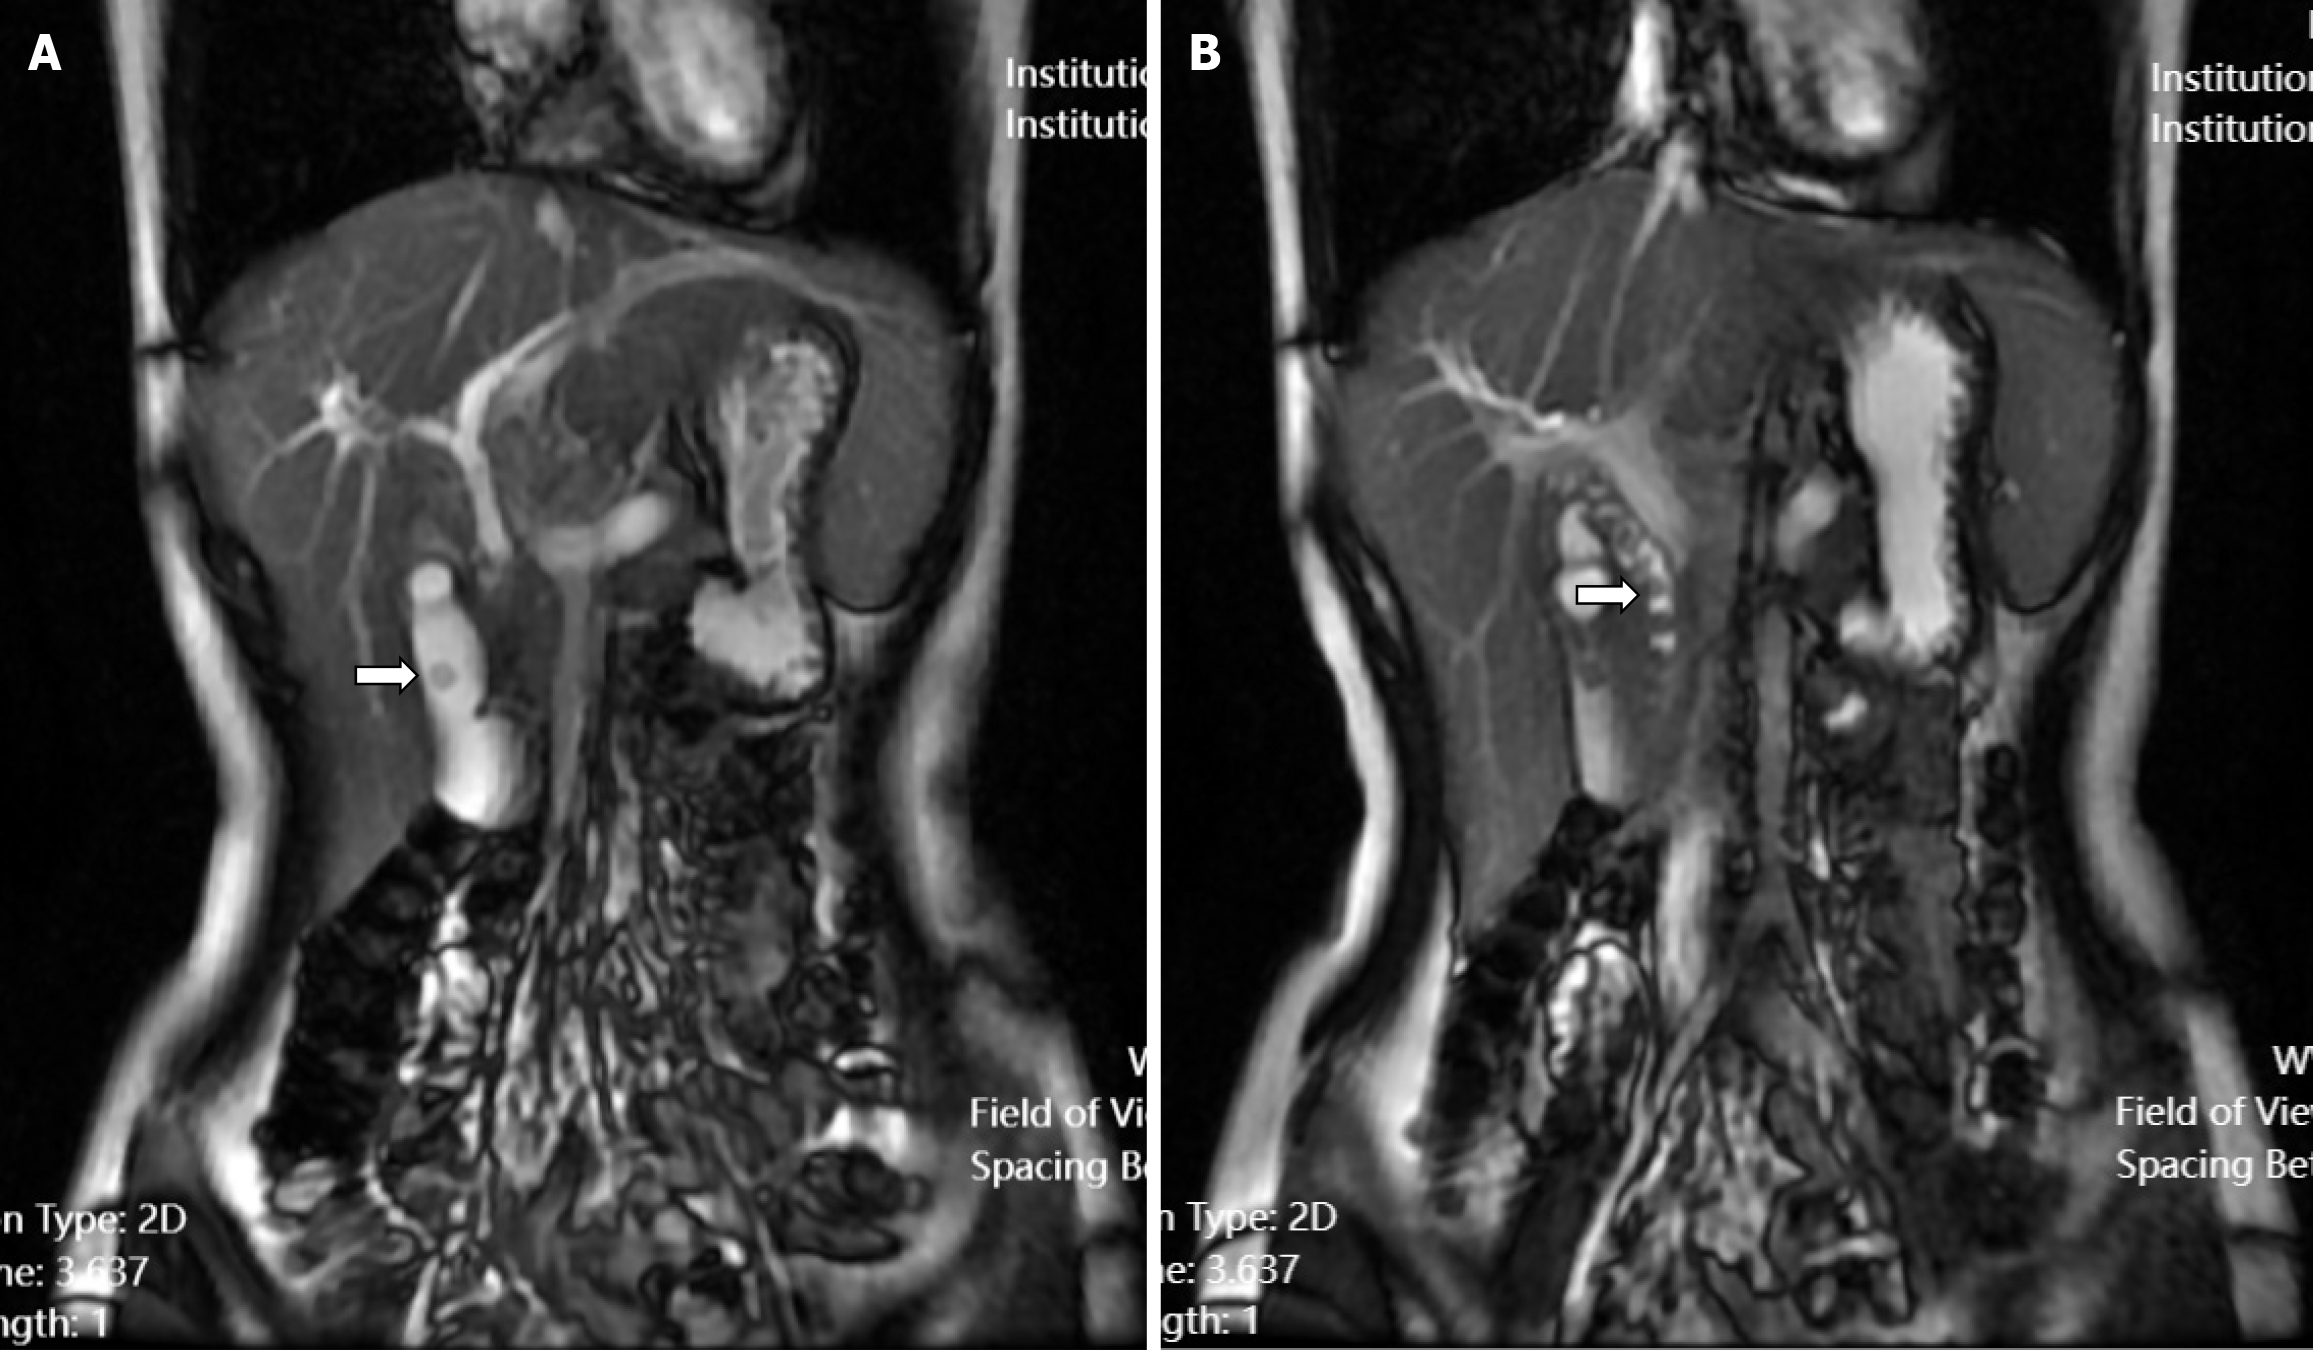

The patient experienced recurrence of upper abdominal pain and discomfort 2 weeks prior to admission, with symptoms worsening 3 days before presentation. On August 12, 2023, she was admitted to the Guangji Hospital. Abdominal ultrasonography revealed choledochal stones, dilated intra- and extrahepatic bile ducts, gallbladder stones, and cholecystitis. Subsequent magnetic resonance cholangiopancreatography confirmed the presence of a gallbladder stone and multiple CBD stones (Figure 1). The patient received symptomatic treatment including anti-infective therapy and rehydration, which resulted in symptom improvement.

Plain and enhanced upper abdominal computed tomography performed on August 17, 2023, demonstrated an enlarged gallbladder, a dilated CBD with a maximum diameter of approximately 1.3 cm, and a slightly dilated main pancreatic duct (Figure 3).